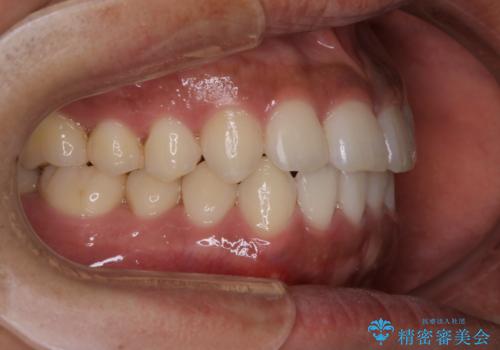

- 上下の前歯のがたつきが気になるとご相談にいらした方です。光加速矯正装置(オルソパルス)を用いて短期間で仕上げることが出来ました。

一般的に噛む力が強い方は矯正治療に時間がかかると言われてます。光加速矯正装置(オルソパルス)を用いることで短期間で仕上げることができました。